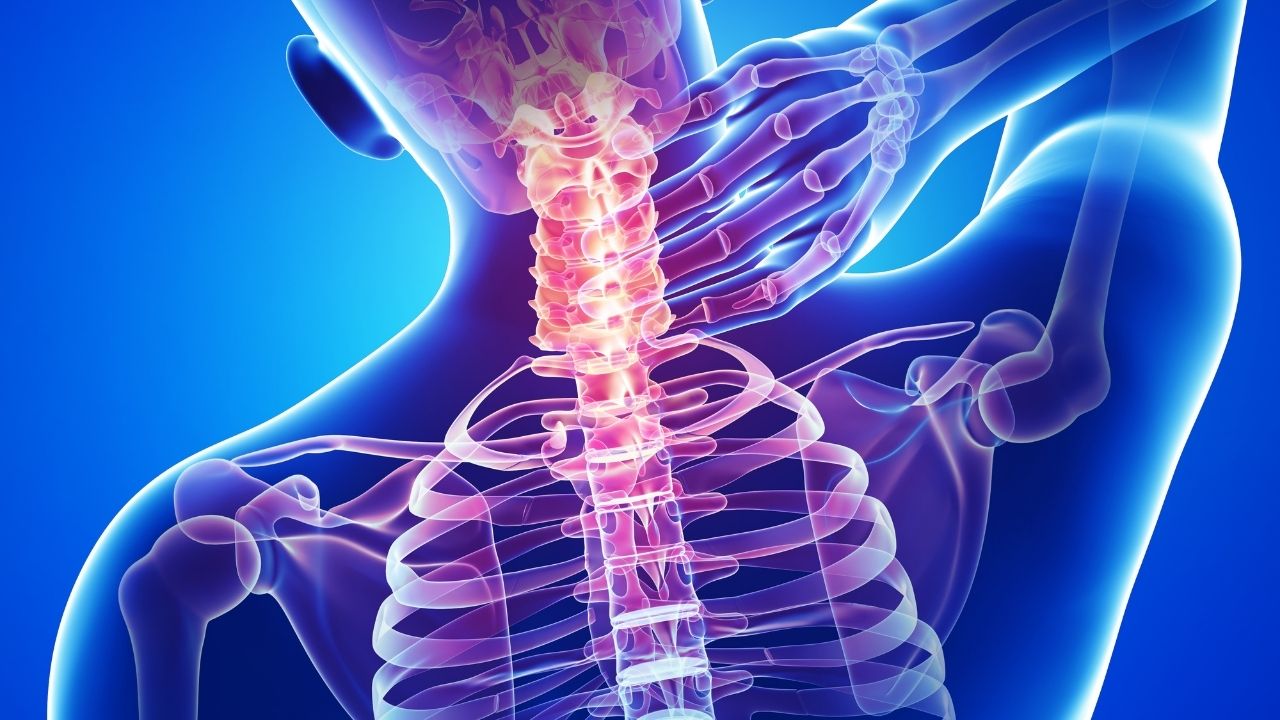

Atuação em hérnia de disco, fraturas da coluna, escoliose, estenose vertebral e processos degenerativos.

Cuidados para aliviar compressões nervosas e melhorar qualidade de vida.